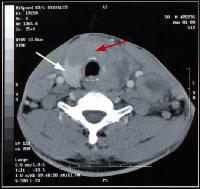

CT-scan van de hals

ct hals

Bedoeling van een scan van de hals kan zijn, het opsporen van een deffect er hoogte van de bloedvaten van de hals, of een abnormaal voorkomen van een bepaalde structuur in de hals, vb. een vergrote schildklier.

Een CT-scan van de hals wordt meestal uitgevoerd met contrast.

Uitzonderingen hiervoor zijn de onderzoeken van de schildklier.

Indien er contrast wordt gegeven moet de patiënt minstens vier uur voor het onderzoek nuchter gehouden worden.